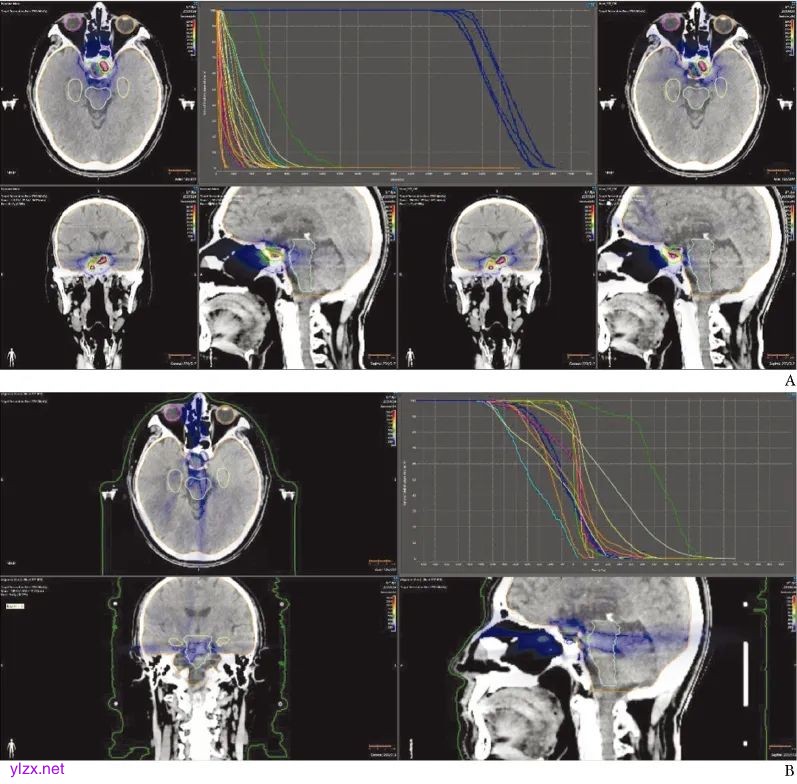

两例患者CyberKnife技术与调强适形放疗计划剂量对比见图1和图2。

图1 患者1采用CyberKnife与普通调强适形放疗计划剂量比较

A.CyberKnife(右)与普通调强适形放疗计划(左)剂量分布;B. CyberKnife与普通调强适形放疗计划剂量差异

两种计划剂量图对比结果显示,CyberKnife技术在不扩大PTV的前提下,可提供更高剂量照射,减少危及器官照射剂量,从而最大限度地减轻组织或器官损伤,实现更加精准的肿瘤放疗,具有显著的剂量学优势。